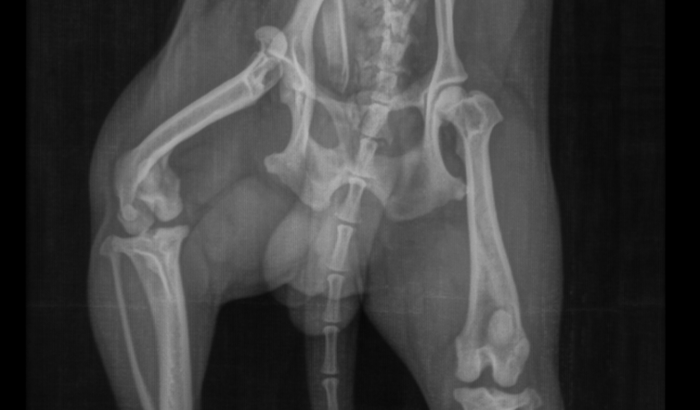

CIRURGIA DO JUSTIN PERNA QUEBRADA

Eu sou Kevin , Venho arrecadar o valor de R$ 1.900,00 Reais , Para fazer a cirurgia da perna quebrada do Justin , Ele está sentindo muita dor .Agradeço a todos. ver tudo

Eu sou Kevin , Venho arrecadar o valor de R$ 1.900,00 Reais , Para fazer a cirurgia da perna quebrada do Justin , Ele está sentindo muita dor .Agradeço a todos.